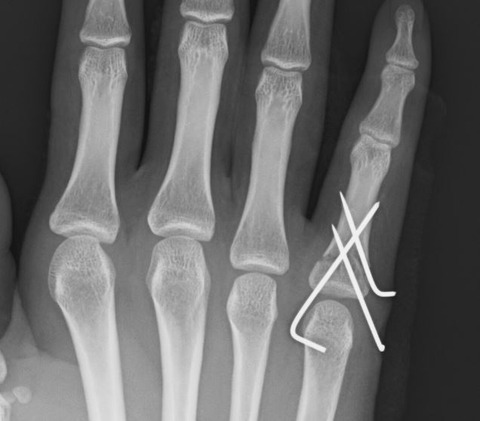

小指基節骨基部骨折で尺・背側転位している症例では、尺・背側から骨折に intrafocal pinningを刺入して整復しています。

麻酔下と言えども、小指を屈曲・橈側に牽引するだけでは整復できないからです。今回の症例では intrafocal pinningに加えてクロスピニングを施行しました。

透視下でも骨折部は安定していたので、疼痛自制内で自動運動を開始する予定です。昔は何度も外来で徒手整復を繰り返していましたが、患者さんにとっては手術の方が楽そうです。